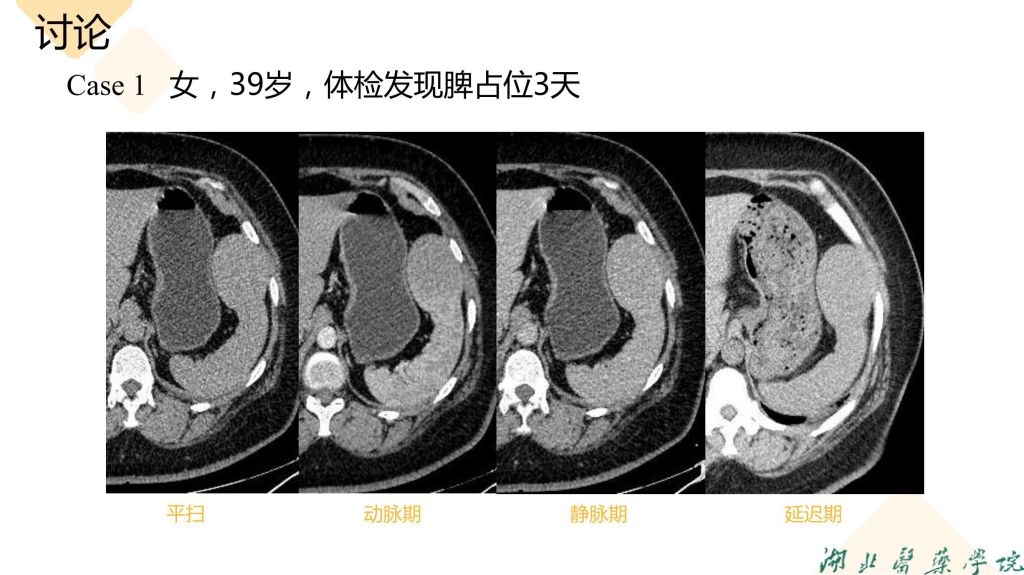

病例分享-脾脏实质性占位性病变

杨雪君 7790必发集团

病例分析-脾脏实性占位性病变-杨雪君.pdf